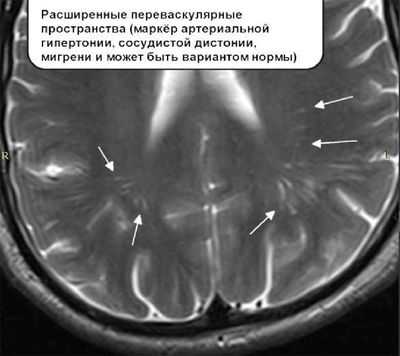

Изменения на МРТ сводятся к наличию очагов разрежения нервной ткани белого вещества (гиподенсивные зоны), расположенных вокруг желудочков или субкортикально, облаковидного лейкоареоза в виде локальных полей демиелинизации вокруг рогов боковых желудочков, в таламусе, стволе мозга, мозжечке. Часто появлению зон ишемии сопутствует расширение боковых желудочков и периваскулярных пространств. Наилучшую картину лейкоареоза можно получить при МРТ в режиме Т2-ВИ.

Расширенные периваскулярные пространства Вирхова-Робина

Периваскулярные пространства Вирхова-Робина — заполненные жидкостью анатомические образования, окружающие отдельные сосуды головного мозга и церебральных оболочек. Их функции связаны с работой иммунитета и дренажем жидкости из нейронов в лимфатические узлы. Расширение этих структур может быть предрасположенностью к патологическим состояниям.

Когда расширение периваскулярных пространств — норма

Увидеть периваскулярные каналы возможно лишь с помощью МРТ.

Часто пространства Вирхова Робина не визуализируются даже на снимках МРТ вследствие их маленькой площади. Имеет значение разрешающая способность томографа. Размер до 2 мм является нормой и встречается у всех людей.

Расширенные периваскулярные пространства называются криблюрами.

Признаки расширенных периваскулярных пространств на МРТ

Их увеличение не всегда свидетельствует о патологии. Механизм их расширения изучается до сих пор. Это возможно вследствие воспаления стенки сосуда, когда последняя истончается и становится более проницаемой. Вышедшая жидкость приводит к расширению криблюр. Другой причиной является нарушение тока ликвора, а еще одной удлинение сосудов.

Ученые и практикующие врачи не пришли к единому мнению, что считать патологией, а что нет. Как правило, фиксирование пространств на МРТ-снимках у людей старшей возрастной группой является вариантом нормы.

Появляются симметрично. Наиболее часто расширение периваскулярных пространств происходит в области нижних базальных структур и очень редко в мозжечке. Как правило, размеры не превышают более 5 мм.

В периваскулярных каналах течет ликвор, поэтому на МРТ криблюры имеют одинаковую плоскость с последним и выглядит изоденсивными.

Существует 2 проекции, в которых обычно производятся МРТ-снимки головного мозга: фронтальная и аксиальная. В первом случае расширенные пространства выглядят в виде полос, а во втором принимают круглую или овальную форму, соответствующую сечению.

В диагностике помогает использование различных МРТ-режимов, особенно T-2. В этом режиме Вирхов-Робинские пространства не имеют более темного ободка вокруг заполненной области, что свидетельствует о том, что это именно часть субарахноидальной оболочки, а не стенка полости, очага или новообразования.